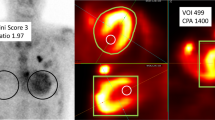

Time dependence of uptake parameters and correlations

Table 4 and Figure 4 summarize the uptake parameters of the 13 patients who were assessed by 99mTc-PYP SPECT/CT at 1 and 3 hours after 99mTc-PYP injection. The CPV1.4 and 1.6, CPA, myocardial SUVmax, aortic blood pool SUVmax, SUVmax ratios, H/CL ratio, and visual grading score were significantly higher at 1 hour than at 3 hours. In contrast, vertebral SUVmax was significantly higher at 3 hours than at 1 hour. Paraspinal muscle SUVmax did not significantly differ between 1 and 3 hours.

Comparison of parameters between 1 and 3 h after injecting 99mTc-PYP into 13 patients with ATTR-CM who were assessed twice. (A) Myocardial SUVmax, aortic blood pool SUVmax, vertebral SUVmax, and paraspinal muscle SUVmax, and (B) myocardial SUVmax/aortic blood pool SUVmax, myocardial SUVmax/vertebral SUVmax, and SUVmax retention index. Green and blue lines indicate means and standard deviations, respectively. Box plot indicates medians, 25%, and 75% quartiles with whiskers at both ends. SUV, standardized uptake value. *P < .05

Table 5 summarizes correlations between uptake parameters and the four prognostic factors in patients with SPECT/CT images acquired at 1 and 3 hours after 99mTc-PYP injection. Figure 5 shows representative correlations between CPV and the four prognostic factors. Table 5 shows significant correlations between the volumetric parameters CPV1.4 and CPA1.4 and the four prognostic factors at 1 and 3 hours. Correlations between volumetric parameters and LVEF, ECV, or troponin T were equivalent between 1 and 3 hours. Correlations between volumetric parameters and GLS were slightly closer at 1 hour than at 3 hours in six patients. The SUVmax retention index closely correlated with LVEF, GLS, and ECV at 1 hour, but the correlation coefficients decreased at 3 hours.